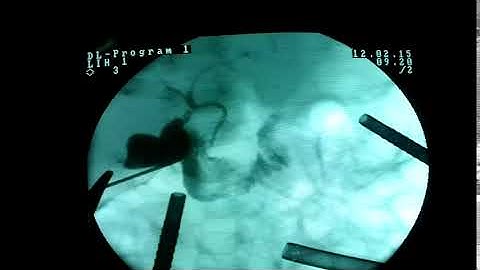

Neonatal Cholangiogram NEO